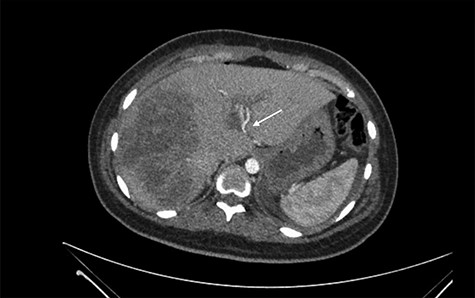

She was referred to our center on postoperative Day 4 due to progressive jaundice and encephalopathy. A triphasic contrast-enhanced abdominal computed tomography (CT) was done revealing a right liver lobe infarct, absence of the right and left hepatic arteries (Fig. 1), presence of an accessory left hepatic artery from the left gastric artery (Fig. 2) and right portal vein thrombosis with extension to the main portal vein (Fig. 3).

Right liver lobe necrosis and absence of proper hepatic artery on the arterial phase of the triphasic contrast-enhanced abdominal CT.